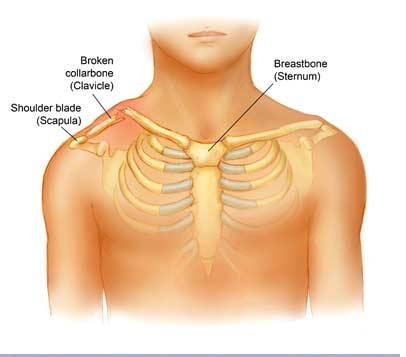

The Clavicle is part of your shoulder and connects your rib cage to your arm.

The Clavicle lies above several important nerves and blood vessels. However, these vital structures are rarely injured when the Clavicle breaks, even though the bone ends can shift when they are fractured.

The clavicle is a long bone and most breaks occur in the middle of it. Occasionally, the bone will break at its ends, where it attaches at the ribcage or Shoulder blade.

- A deformity or "bump" over the break

- Bruising, swelling, and/or tenderness over the collarbone